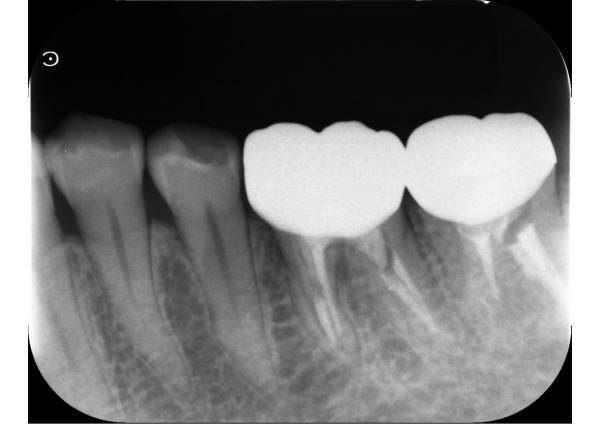

お口の中を見てみると、左下6番目の歯ぐきにサイナストラクト(歯根の炎症が原因でできる、膿の出口となる穴)が認められました。口腔内エックス線画像から、残っている歯根が薄いため、破折している可能性をお伝えしました。

歯根の状態をさらに詳しく調べるため、セラミックを外してサイナストラクトに造影性のあるゴムを挿入し、再度、口腔内エックス線検査を行いました。破折した部位からの細菌感染により、歯根に沿って深く骨がなくなっていました。また、口腔内カメラで破折した部位を確認し、保存は難しく、抜歯となりました。

5日目〜8日目 サイナストラクトを認めたため、デンタルエックス線を撮影し、歯根破折の疑いがあると説明しました。セラミックを外して破折した部位を確認するため、造影性のあるゴムを写して再度撮影しました。